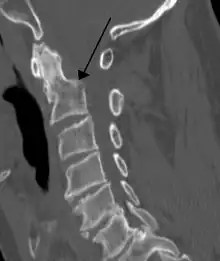

A fracture of the base of the dens as seen on CT

- Type II fracture - Extends through the base of the dens. It is the most commonly encountered fracture for this region of the axis. This type is unstable and has a high rate of non-union.